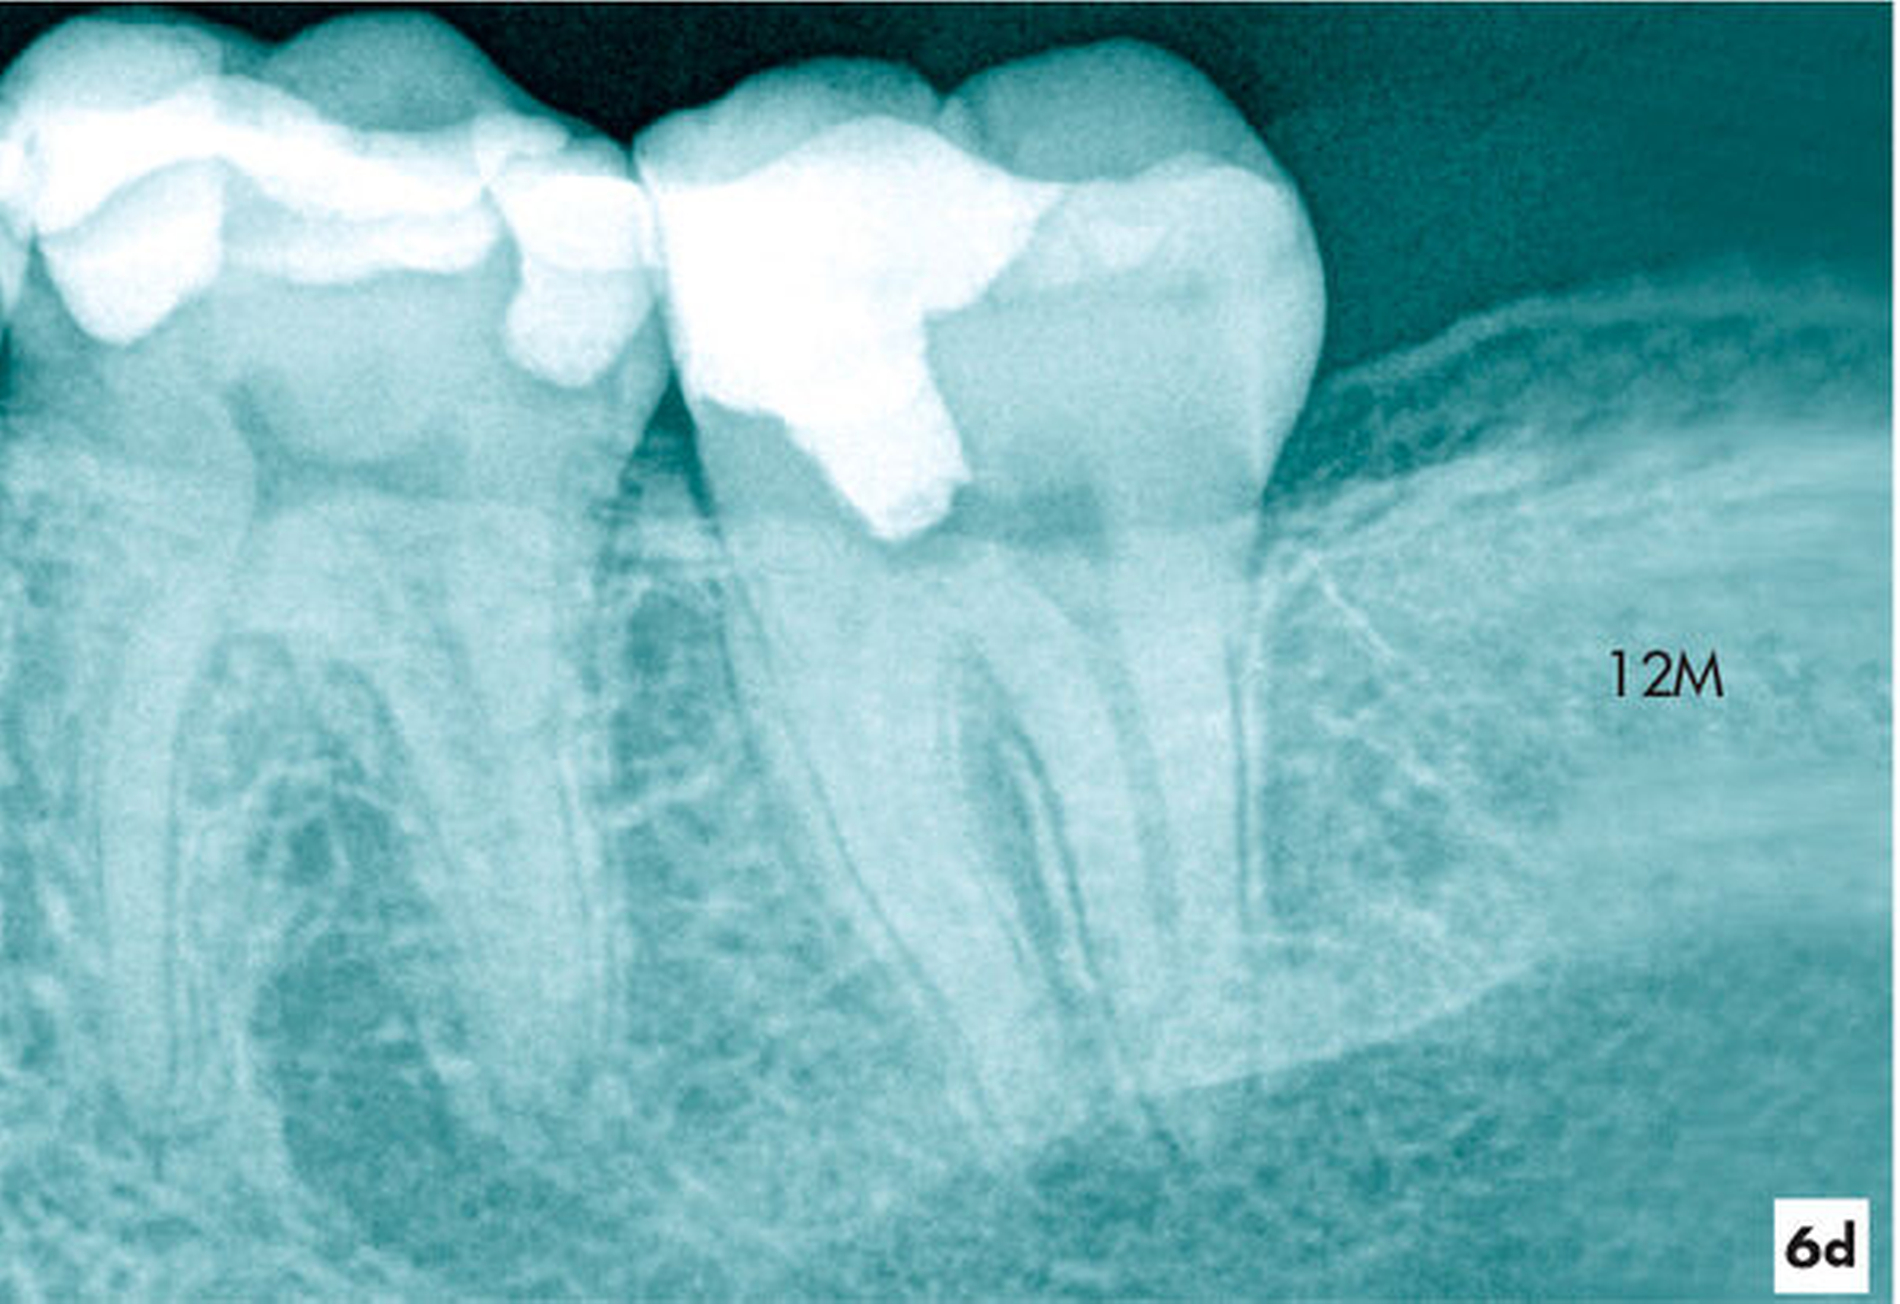

Zum Einjahresrecall reagierte der Zahn auf den thermischen und elektrischen Sensibilitätstest positiv. Die Zahnbeweglichkeit war physiologisch und röntgenologisch erschien der Desmodontalspalt im Vergleich zum Ausgangsbild in normaler Breite (Abbildung 6d).